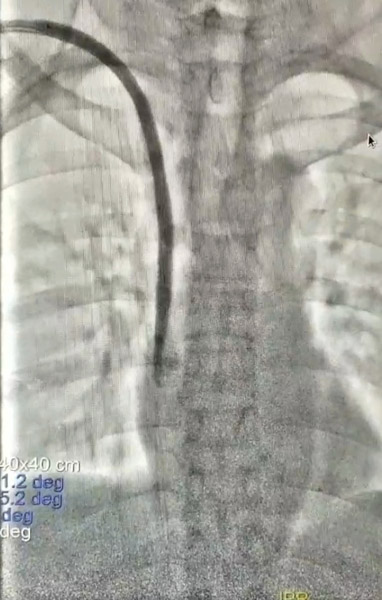

翌日,覃女士被送入了介入室,醫生經患者原留置長期導管靜脈端植入導絲,并經導絲植入球囊擴張血透導管,使其與周圍粘連組織松解,然后再次牽拉導管,最終順利將導管拔除。

柳州市人民醫院堅持以人民為中心,持之以恒做到廉潔行醫、精誠大醫。此次血管外科為患者實施的經導管內球囊擴張輔助拔除嵌頓血液透析導管術在柳州市人民醫院尚屬首例,手術創傷極小,避免了更大創傷性操作取管,取得了良好的療效,為患者解除了困擾。